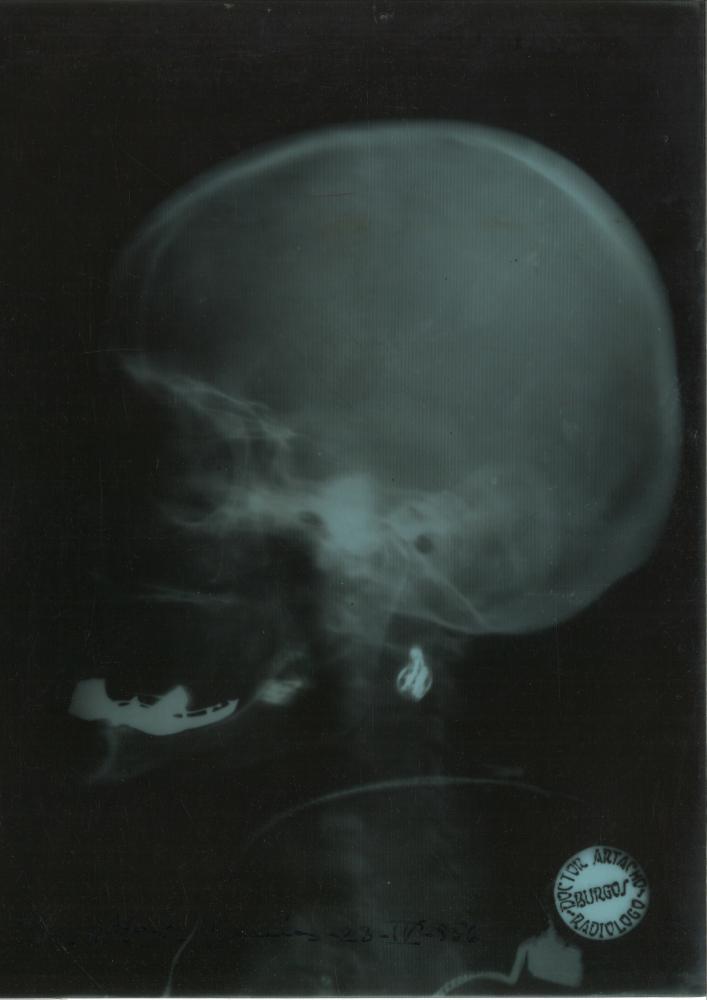

Los fondos documentales fueron donados por su hijo Rafael Vara Thorbeck e ingresaron en el Archivo el 12 de mayo de 2000. Están formados por historias clínicas y fichas de diagnósticos y tratamientos de pacientes entre 1927 y 1977, atendidos en el Hospital Provincial de Burgos, La Clínica del Dr. Vara y la Clínica de San Francisco de Asís de Madrid, documentación económica y de administración de las clínicas, correspondencia profesional y personal y documentación relacionada con su actividad docente: discursos, conferencias, curricula de alumnos, diapositivas, etc. y algunas fotografías.